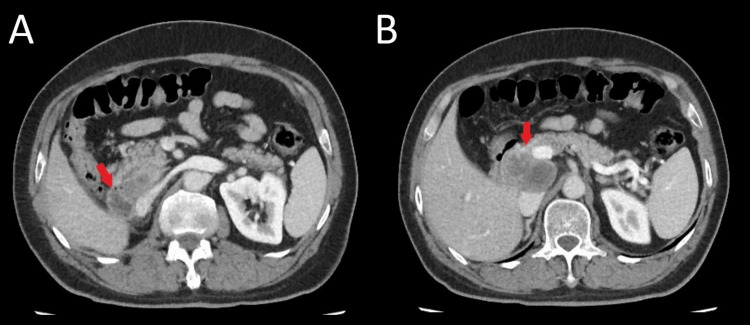

Hence, he was put on nivolumab for six months and at the end of the treatment he showed complete radiologic response according to Response Evaluation Criteria in Solid Tumors (RECIST) in the lungs and the brain, as well as complete resolution of metastatic lesions in the abdominal wall and liver, except for the persistence of a mass in duodenohepatic region (Figure 4).

Unfortunately, nivolumab was discontinued because of financial limitations. He was started on bevacizumab 400 mg every two weeks and was on maintenance bevacizumab for 22 months. On July 2022 the patient became icteric again with high levels of direct bilirubin. A CT scan revealed an 82×50×35 mm mass in the duodenohepatic region compressing the common bile duct (CBD), with no other sign of metastatic lesions in the chest, brain or abdominopelvic CT scans (Figures 5, 6). He is now being managed by a multidisciplinary team to determine the next therapeutic options.